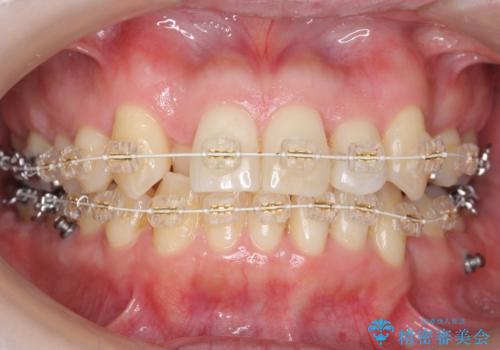

40代の矯正 八重歯を綺麗に

- 40代女性

- 審美装置

- 2年3ヶ月

- 前歯のガタガタを主訴に来院。

・正中を顔にしっかり合わせるには、上下左右4本抜歯

・出来るだけ合わせる程度でよければ、左のみ上下2本抜歯。但し上下正中は揃わないかもしれない。

を提案し、

2本抜歯を選択されました。

矯正用のミニスクリューを使用し、また、前歯をIPRすることで正中の左へのずれを最小限に抑えています。

上の前歯が内側に入っているクロスバイトは、笑った時に影になってしまい、かなり目立ちます。

内側に入っている前歯を外に出すだけで劇的に印象が変わります。